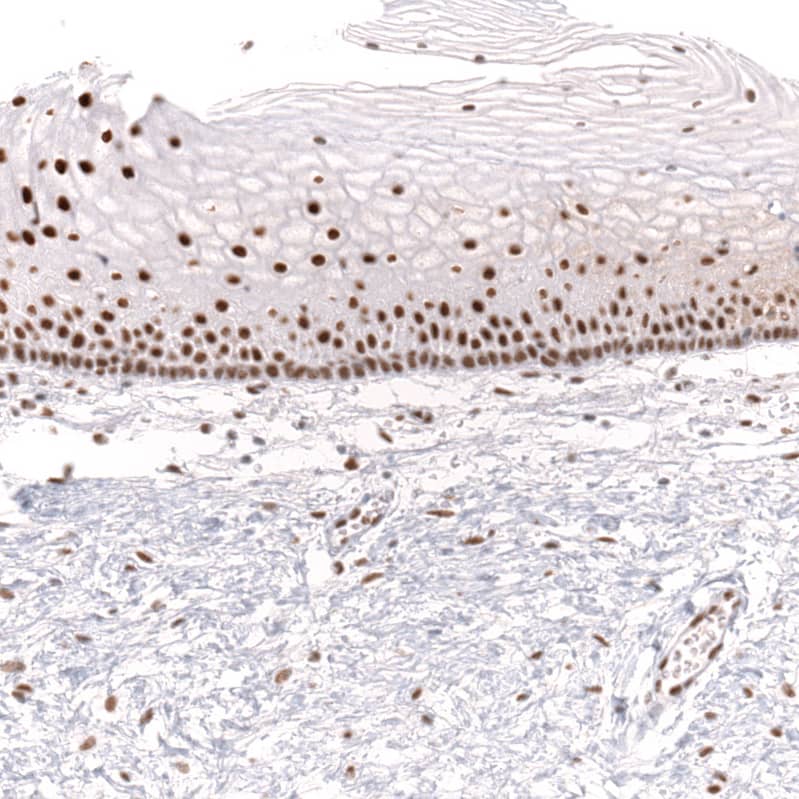

Staining of human uterine cervix shows strong nuclear positivity in squamous epithelial cells.